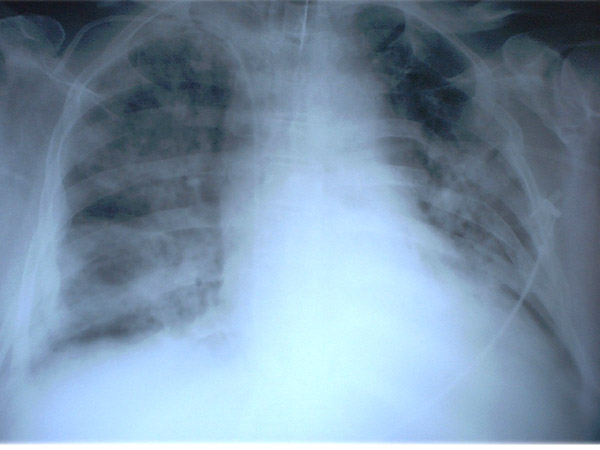

APR Derrame pleural derecho